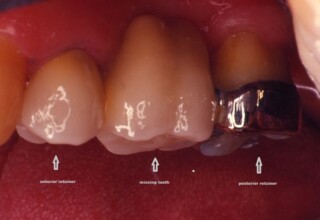

Fixed Restoration combining a classical and a resin-bonded retainer (RBR)

A missing upper premolar was replaced by a fixed bridge. The anterior abutment was previously restored with a crown, so a classic full coverage crown served as the anterior bridge retainer. The posterior abutment was an unprepared, unfilled tooth with an extensive gingival recession. In order to avoid extensive preparation and a concomitant root canal, a partial metal retainer (a 360o Maryland type wing) was used. It provides adequate retention since 2008.